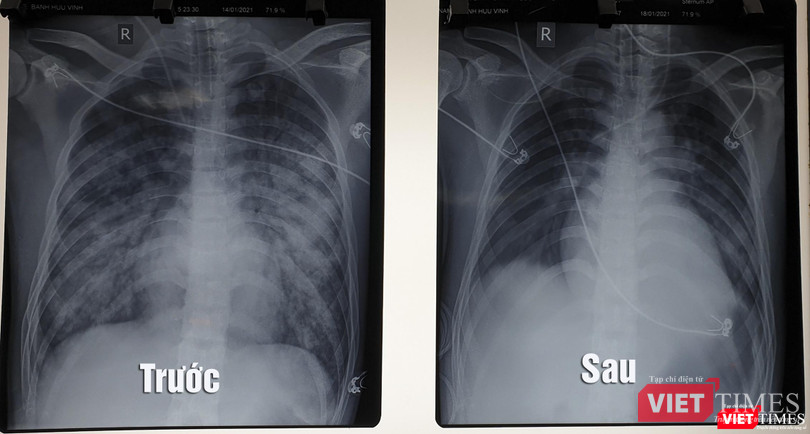

Toàn viện đã hội chẩn tối khẩn với nhiều chuyên khoa, để quyết định can thiệp bằng ECMO, do bệnh nhân vừa sốc tim kết hợp suy hô hấp nặng, phim chụp X quang phổi thâm nhiễm lan tỏa hai phế trường nên kíp hội chẩn hội ý dùng phương pháp can thiệp song song vừa hỗ trợ tim và hỗ trợ phổi nhân tạo cùng lúc (phương pháp VAV ECMO), kết hợp với các phương pháp điều trị hỗ trợ tích cực khác như thở máy, lọc máu liên tục, lọc thận cấp cứu và hồi sức tim mạch nâng cao.

| Hình ảnh X quang phổi của bệnh nhân trước và sau khi điều trị bằng kỹ thuật ECMO (Ảnh: BVCC) |